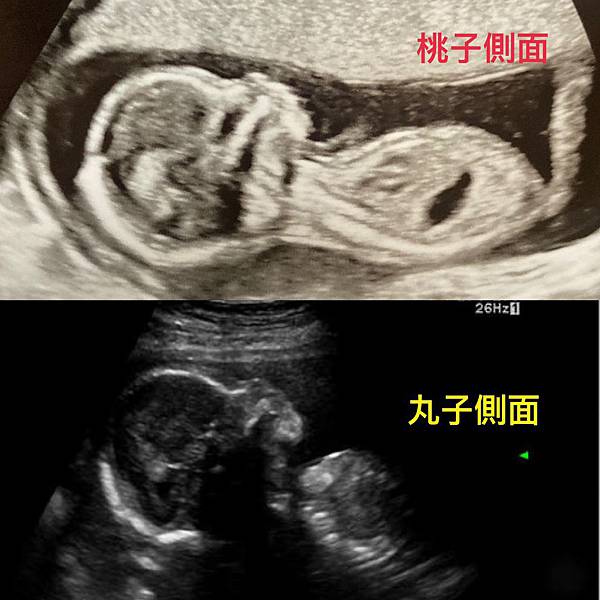

(桃子跟丸子的側面看起來好像XD)從第12周開始就是大家所說的穩定期